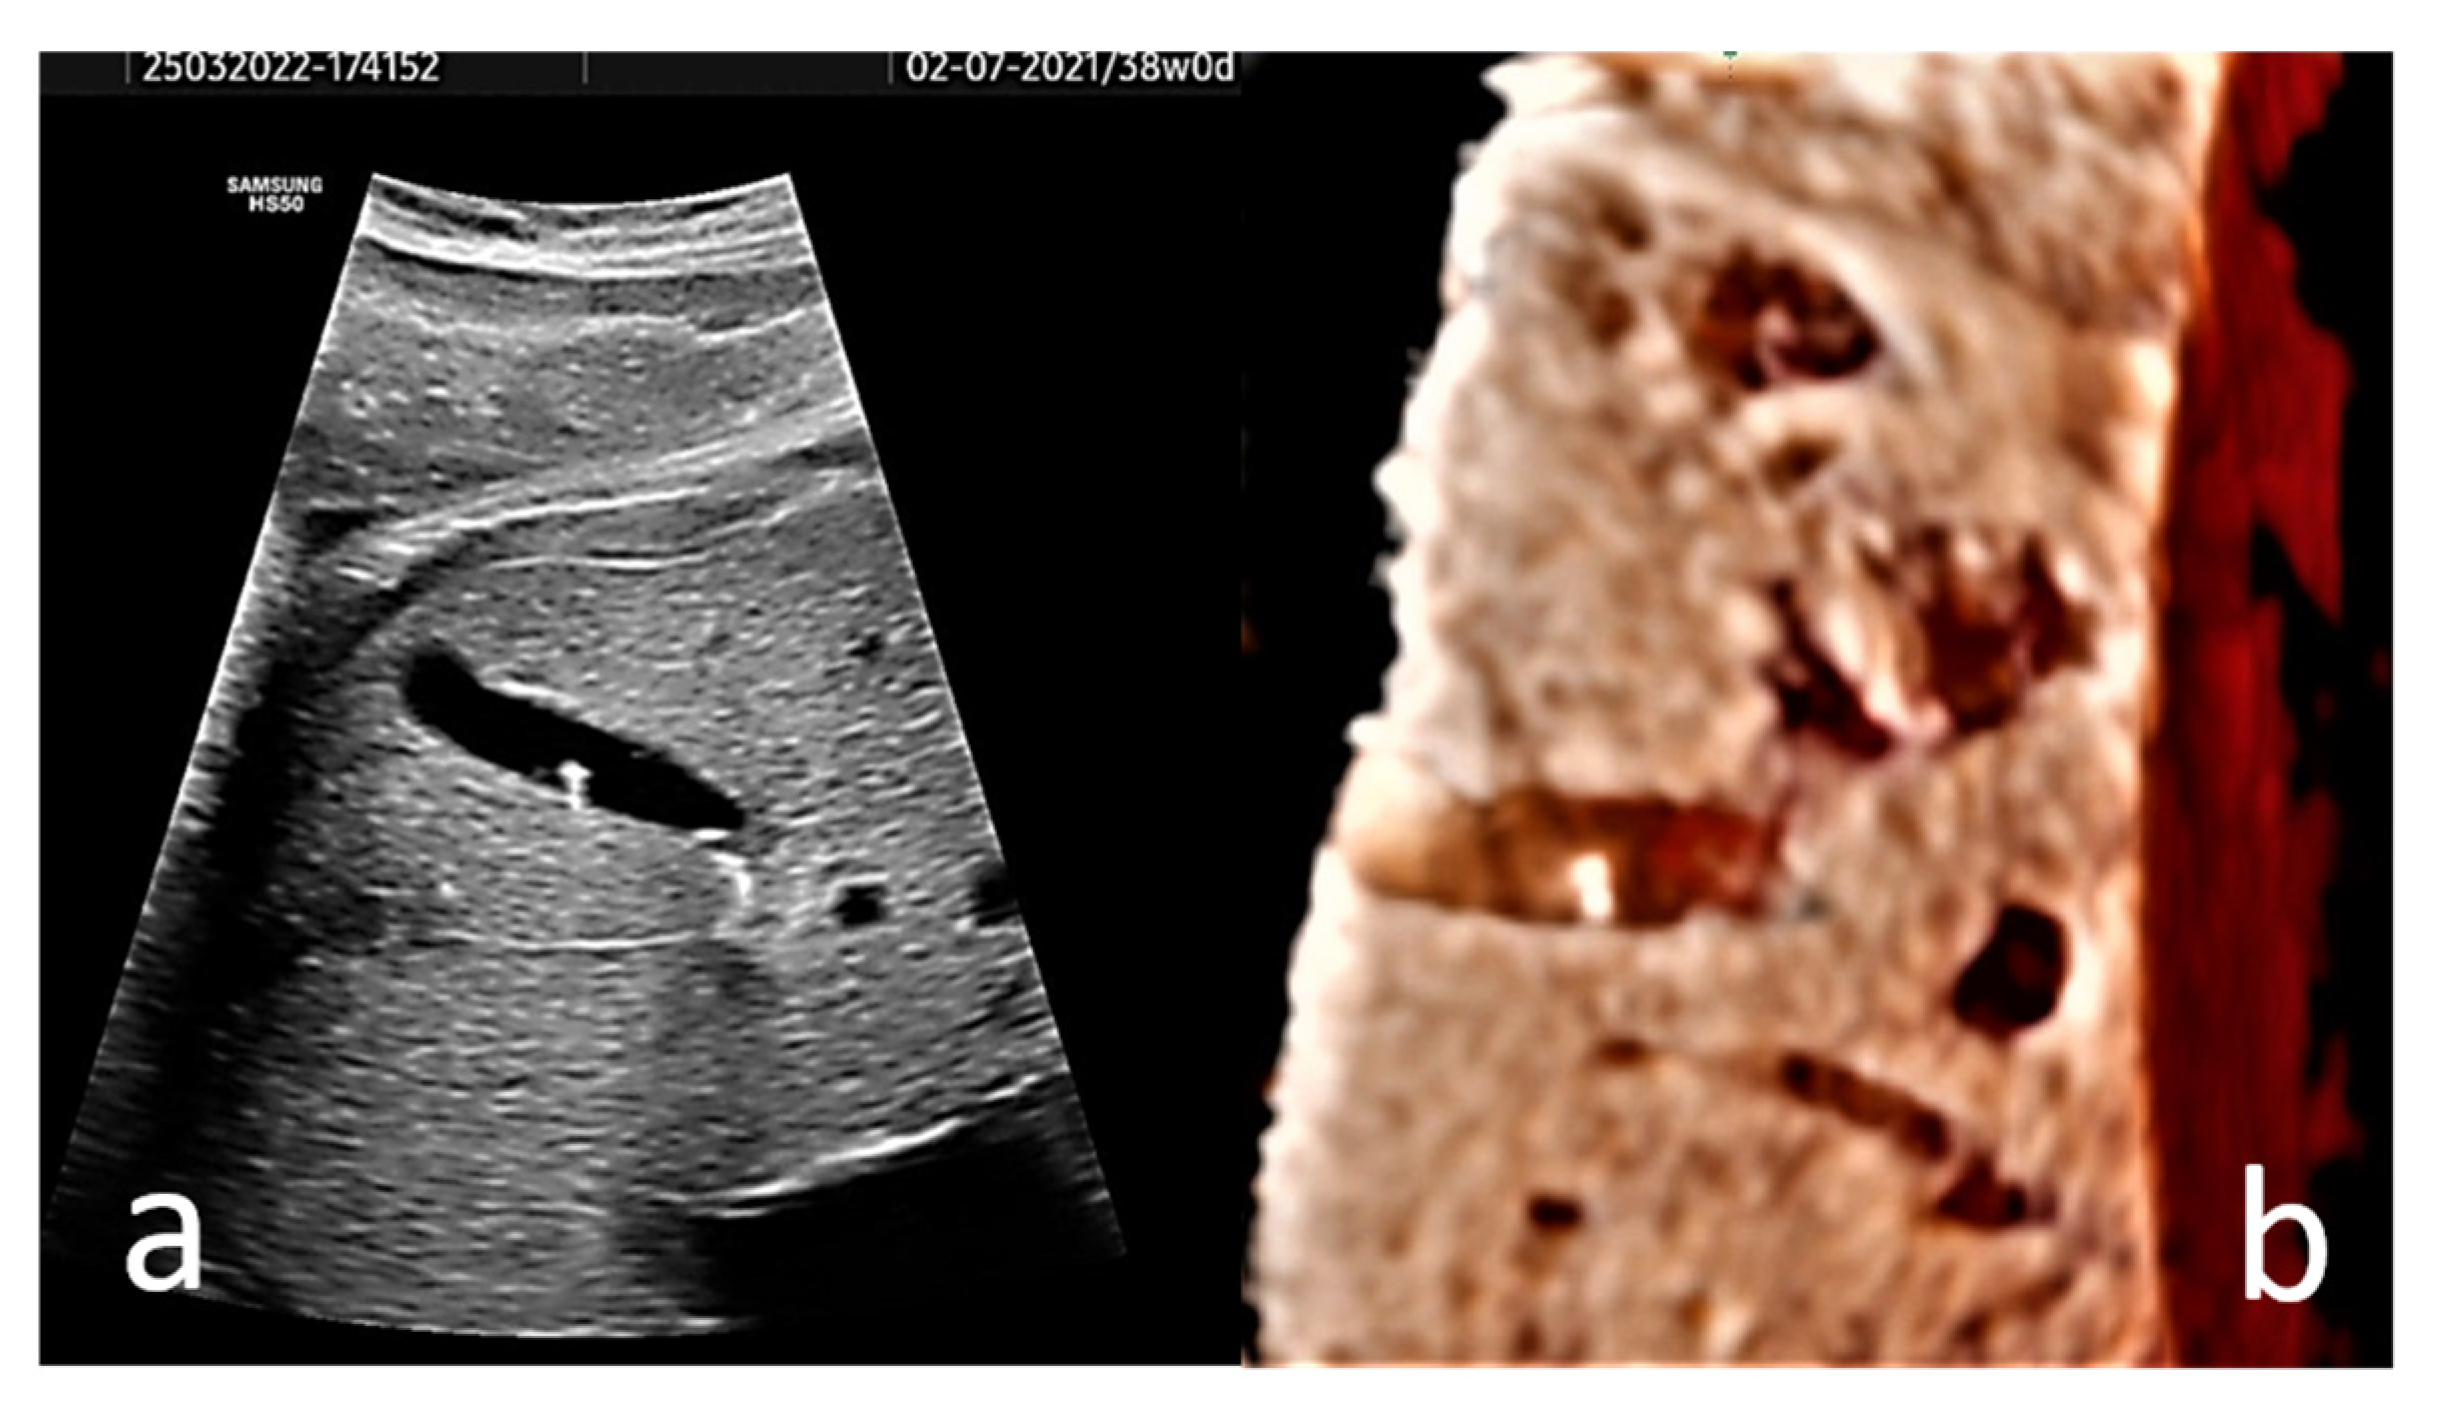

EC may present in the form of hyperechogenic images, or homogenous echogenic material filling the gallbladder (sludge). Single or multiple hyperechogenic foci are typically confined, well-defined US images with a diameter of less than 1 cm (Figure 2, and Video S1). Due to their shining aspect, they produce a plastic image that we named “starry sky gallbladder” when present in multiples. They may be mobile inside the gallbladder lumen [15,19,27]. We interpret the “mobility” of EC as changes in the position of the hyperechogenic spots between consecutive exams, and not the floating of these structures under the influence of gravitation. The sludge could represent a thickening of the bile or a stage in the spontaneous dissolution of gallstones [6]. It has been stated that 40% of EC manifest sonographically as sludge [3].

Figure 2.

(a) Axial section of the gallbladder of a 38 gestational weeks fetus. The hyperechogenic spots are well-defined and do not present distal shadowing; instead they show comet tail artifact. (b) A 3D rendered image of the fetus’ gallbladder is provided. A Voluson S8 ultrasound machine with abdominal convex array volume probe RAB6-RS (GE Healthcare, Zipf, Austria) was used.

In our opinion, the diagnostic value of 3D ultrasonography for fetal EC is reduced since the images provided by several studies [29,30] are unimpressive. Without the need for 3D US imaging, the diagnosis is easy and anatomically correct with 2D US. To illustrate this idea, a 3D US rendered image of the fetus’ gallbladder is provided (Figure 2b).